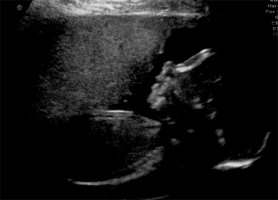

Egal, heute hatte ich ja die zweite Organdiagnose weil der Krümmel beim ersten mal nicht alles gezeigt hat, hach das war toll!

Ich häng mal ein Bildchen an.

27cm ist er jetzt wohl schon groß und wiegt knapp 400g. Bäuchlein hab ich auch.. ok den hatte ich vorher schon.. aber er sieht jetzt anders aus *s*

Anhänge

• ultraschall.jpg

ultraschall.jpg

55,8 KB · Aufrufe: 223